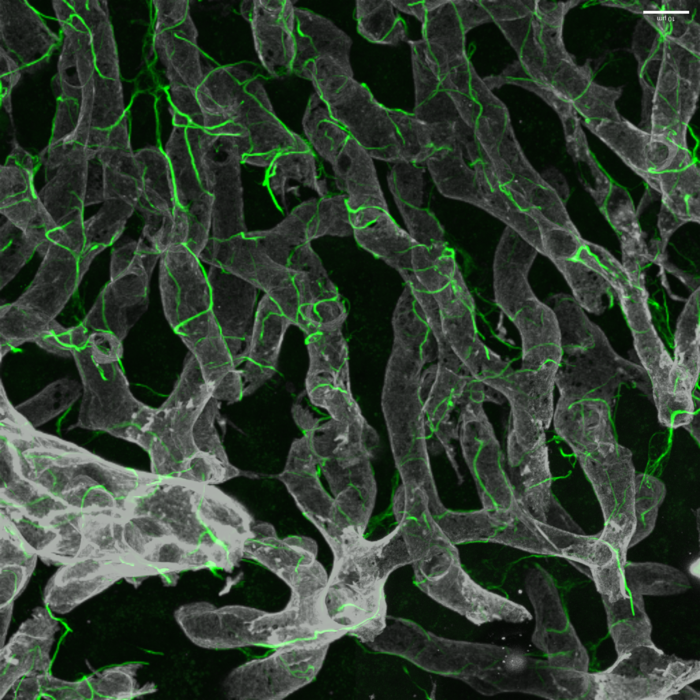

在健康的肝臟中,肝臟星狀細胞及其復雜的細胞投影(綠色)包裹在血管(灰色)周圍。

利用最新的技術——包括小鼠和人類肝組織的單核測序和先進的小鼠3D玻璃成像來表征關鍵的產生瘢痕的肝細胞——研究人員發現了治療非酒精性脂肪性肝病(NAFLD)的新的候選藥物靶點。這項研究是由西奈山伊坎醫學院的研究人員領導的。

“我們的目的是了解這種纖維化瘢痕的基礎,并通過研究肝星狀細胞(肝臟中關鍵的瘢痕生成細胞),確定可能導致晚期NASH新治療方法的藥物靶點,”高級研究作者Scott L. Friedman博士說?!敖Y合這種新的玻璃肝臟成像方法——一種先進的組織清除方法,能夠深入洞察——以及單個星狀細胞的基因表達分析,我們對這些細胞如何在NASH進展到晚期時產生瘢痕有了全新的理解?!?/p>

研究人員發現,在晚期疾病中,星狀細胞之間形成了一個密集的相互作用網絡,從而促進了這68個以前沒有在這種疾病中發現的獨特相互作用對。